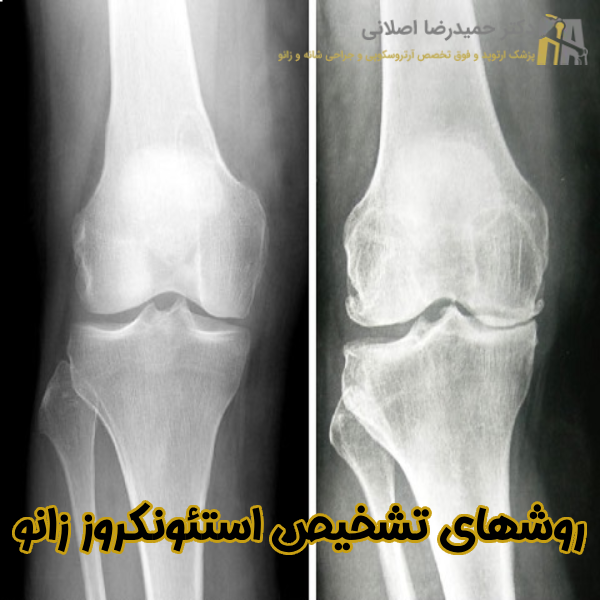

روشهای تشخیص استئونکروز زانو

بهتر است بدانید تشخیص زودهنگام نکروز آواسکولار اهمیت ویژه ای در پیشگیری از پیشرفت بیماری و تخریب مفصل زانو دارد. همانطور که در بالا ذکر کردیم این عارضه در روزهای ابتدایی ممکن است با علائم واضح همراه نباشد به همین دلیل به بهترین متخصص ارتوپد تهران مراجعه نمایید تا با معاینه فیزیکی یا تجویز روشهای تشخیص پیشرفته علت این بیماری را شناسایی شود. به طور کلی روشهای تشخیص این بیماری به شرح زیر است:

- تصویربرداری با اشعه ایکس (X-ray)